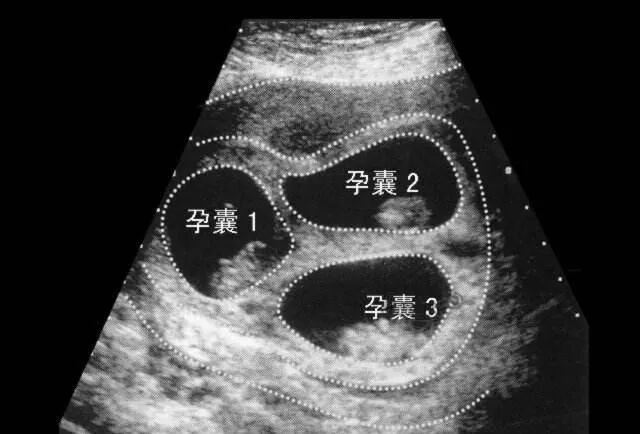

数据表明,若行双胚胎移植,其多胎妊娠率超过30%~40%,是自然妊娠者的20~40倍,其中80%以上为双胎妊娠,少数为三胎以上的妊娠。

囊胚的着床率较卵裂期胚胎高,很多时候为了确保能够顺利妊娠,会移植两枚卵裂期胚胎。如果移植的胚胎都着床了,那么就形成了多胎妊娠。

若超出了女性的身体负荷就要进行减胎手术,而减胎手术也可能存在风险,而单囊胚移植就可以有效的避免多胎妊娠的问题。